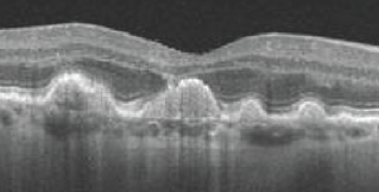

múltiplos DEPS, sugestivo de DMRI

O OCT mostra fluido subretiano, com descolamento do epitélio pigmentar (DEP) em formato de “M”, sugestivo de vasculopatia polipoidal

(hiperfluorescência precoce do pólipo à angiografia com indocianina verde)